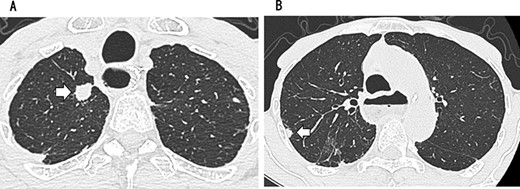

Since no other findings suggestive of distant metastasis were found, partial left lung resection was performed for the two nodules. Both were diagnosed as squamous cell carcinomas (Fig. 4). Furthermore, 5 months after left lung resection, a metastatic liver tumor was found, which was also surgically resected. Finally, 10 years and 4 months after esophagectomy, 3 years after the first lung resection and 1 year after hepatectomy, the patient died due to peritoneal dissemination.

CT revealing a nodule measuring 1.5 cm at the apex of the left lung (A) and a nodule measuring 0.9 cm below the S9 pleura of the left lung (B).